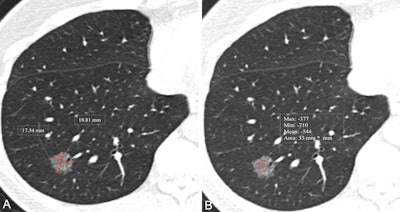

- CT-based model assesses lung lesions from nonsolid nodulesby Amerigo Allegretto

A model based on CT imaging features performed well in a study, differentiating lung lesions from nonsolid nodules.